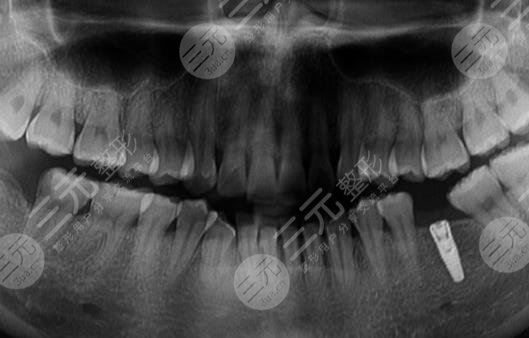

Because the overall condition of my teeth is okay, but it is a little loose, and then the doctor first did an overall examination of my teeth, took a film to determine that I can carry out dental implant surgery, and then set up the plan for me, before the implant first carried out a detailed situation of my teeth, and then the installation of implants, because there is anesthesia, so I don't feel anything, but I can feel that I am doing something on the bone, and it will take about 2 months to carry out the next step after the installation.

Can you take a look at how I looked after the dental implant surgery, is it still relatively good? It looks very natural, and the more important thing is to become particularly strong, like the foods that I didn't dare to eat because of tooth problems before, and I can eat the big bones I like to eat every day, and I am really happy in my heart.